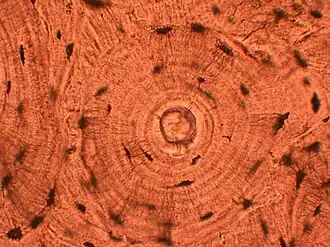

The most commonly used stain in histology is a combination of hematoxylin and eosin (often abbreviated H&E). Hematoxylin is used to stain nuclei blue, while eosin stains the cytoplasm and the extracellular connective tissue matrix of most cells pink. There are hundreds of various other techniques which have been used to selectively stain cells. Other compounds used to color tissue sections include safranin, Oil Red O, congo red, silver salts and artificial dyes. Histochemistry refers to the science of using chemical reactions between laboratory chemicals and components within tissue. A commonly performed histochemical technique is the Perls' Prussian blue reaction, used to demonstrate iron deposits in diseases like Hemochromatosis.[2]